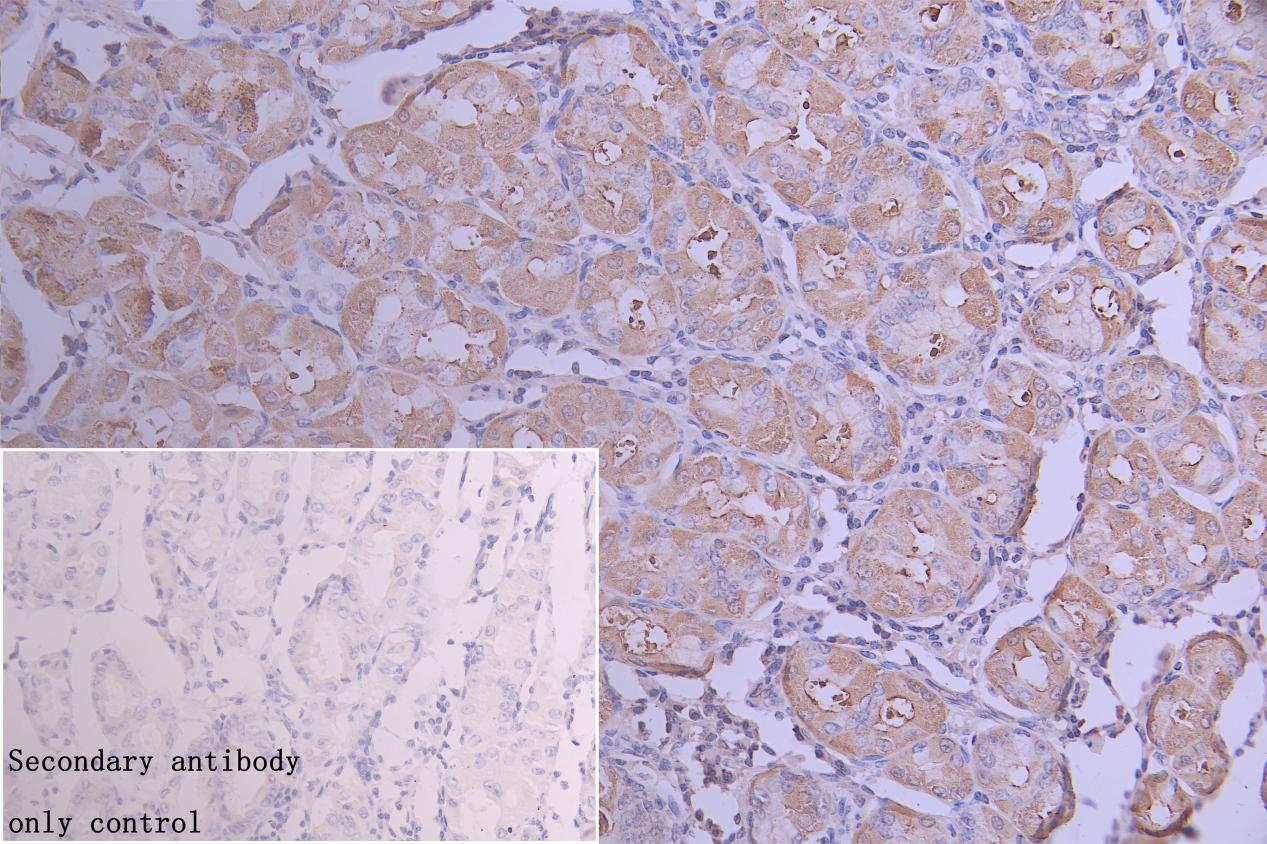

IHC image of CSB-PA887979LA01HU diluted at 1:300 and staining in paraffin-embedded human stomach tissue performed on a Leica BondTM system. After dewaxing and hydration, antigen retrieval was mediated by high pressure in a citrate buffer (pH 6.0). Section was blocked with 10% normal goat serum 30min at RT. Then primary antibody (1% BSA) was incubated at 4°C overnight. The primary is detected by a Goat anti-rabbit polymer IgG labeled by HRP and visualized using 0.05% DAB. Secondary antibody only control: uses 1% BSA instead of primary antibody

IHC image of CSB-PA887979LA01HU diluted at 1:300 and staining in paraffin-embedded human gastric tissue performed on a Leica BondTM system. After dewaxing and hydration, antigen retrieval was mediated by high pressure in a citrate buffer (pH 6.0). Section was blocked with 10% normal goat serum 30min at RT. Then primary antibody (1% BSA) was incubated at 4°C overnight. The primary is detected by a Goat anti-rabbit polymer IgG labeled by HRP and visualized using 0.05% DAB. Secondary antibody only control: uses 1% BSA instead of primary antibody